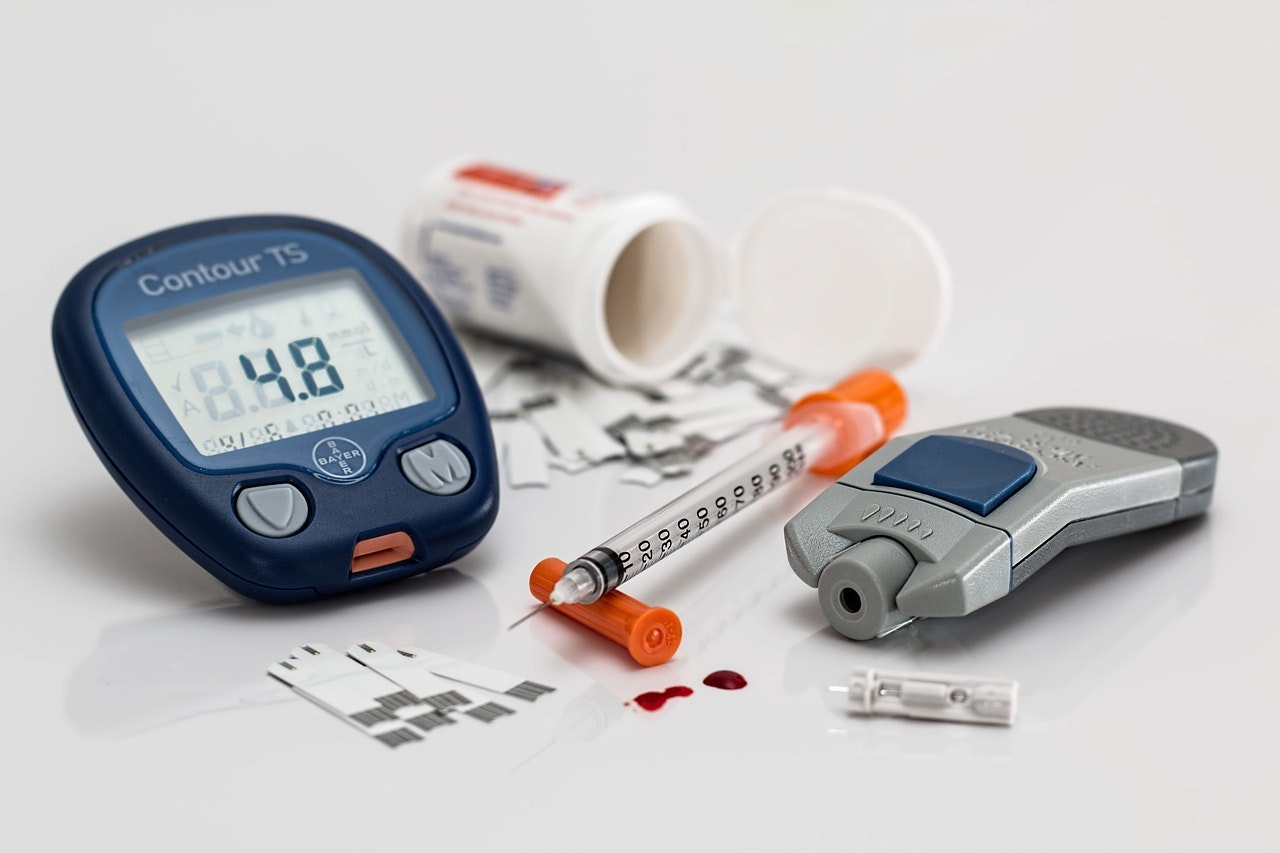

Read moreNavigating Life Insurance with Heart Disease and Diabetes: A Comprehensive Guide

Read moreLife Insurance Underwriting for Diabetics: A Guide to Navigating the Process